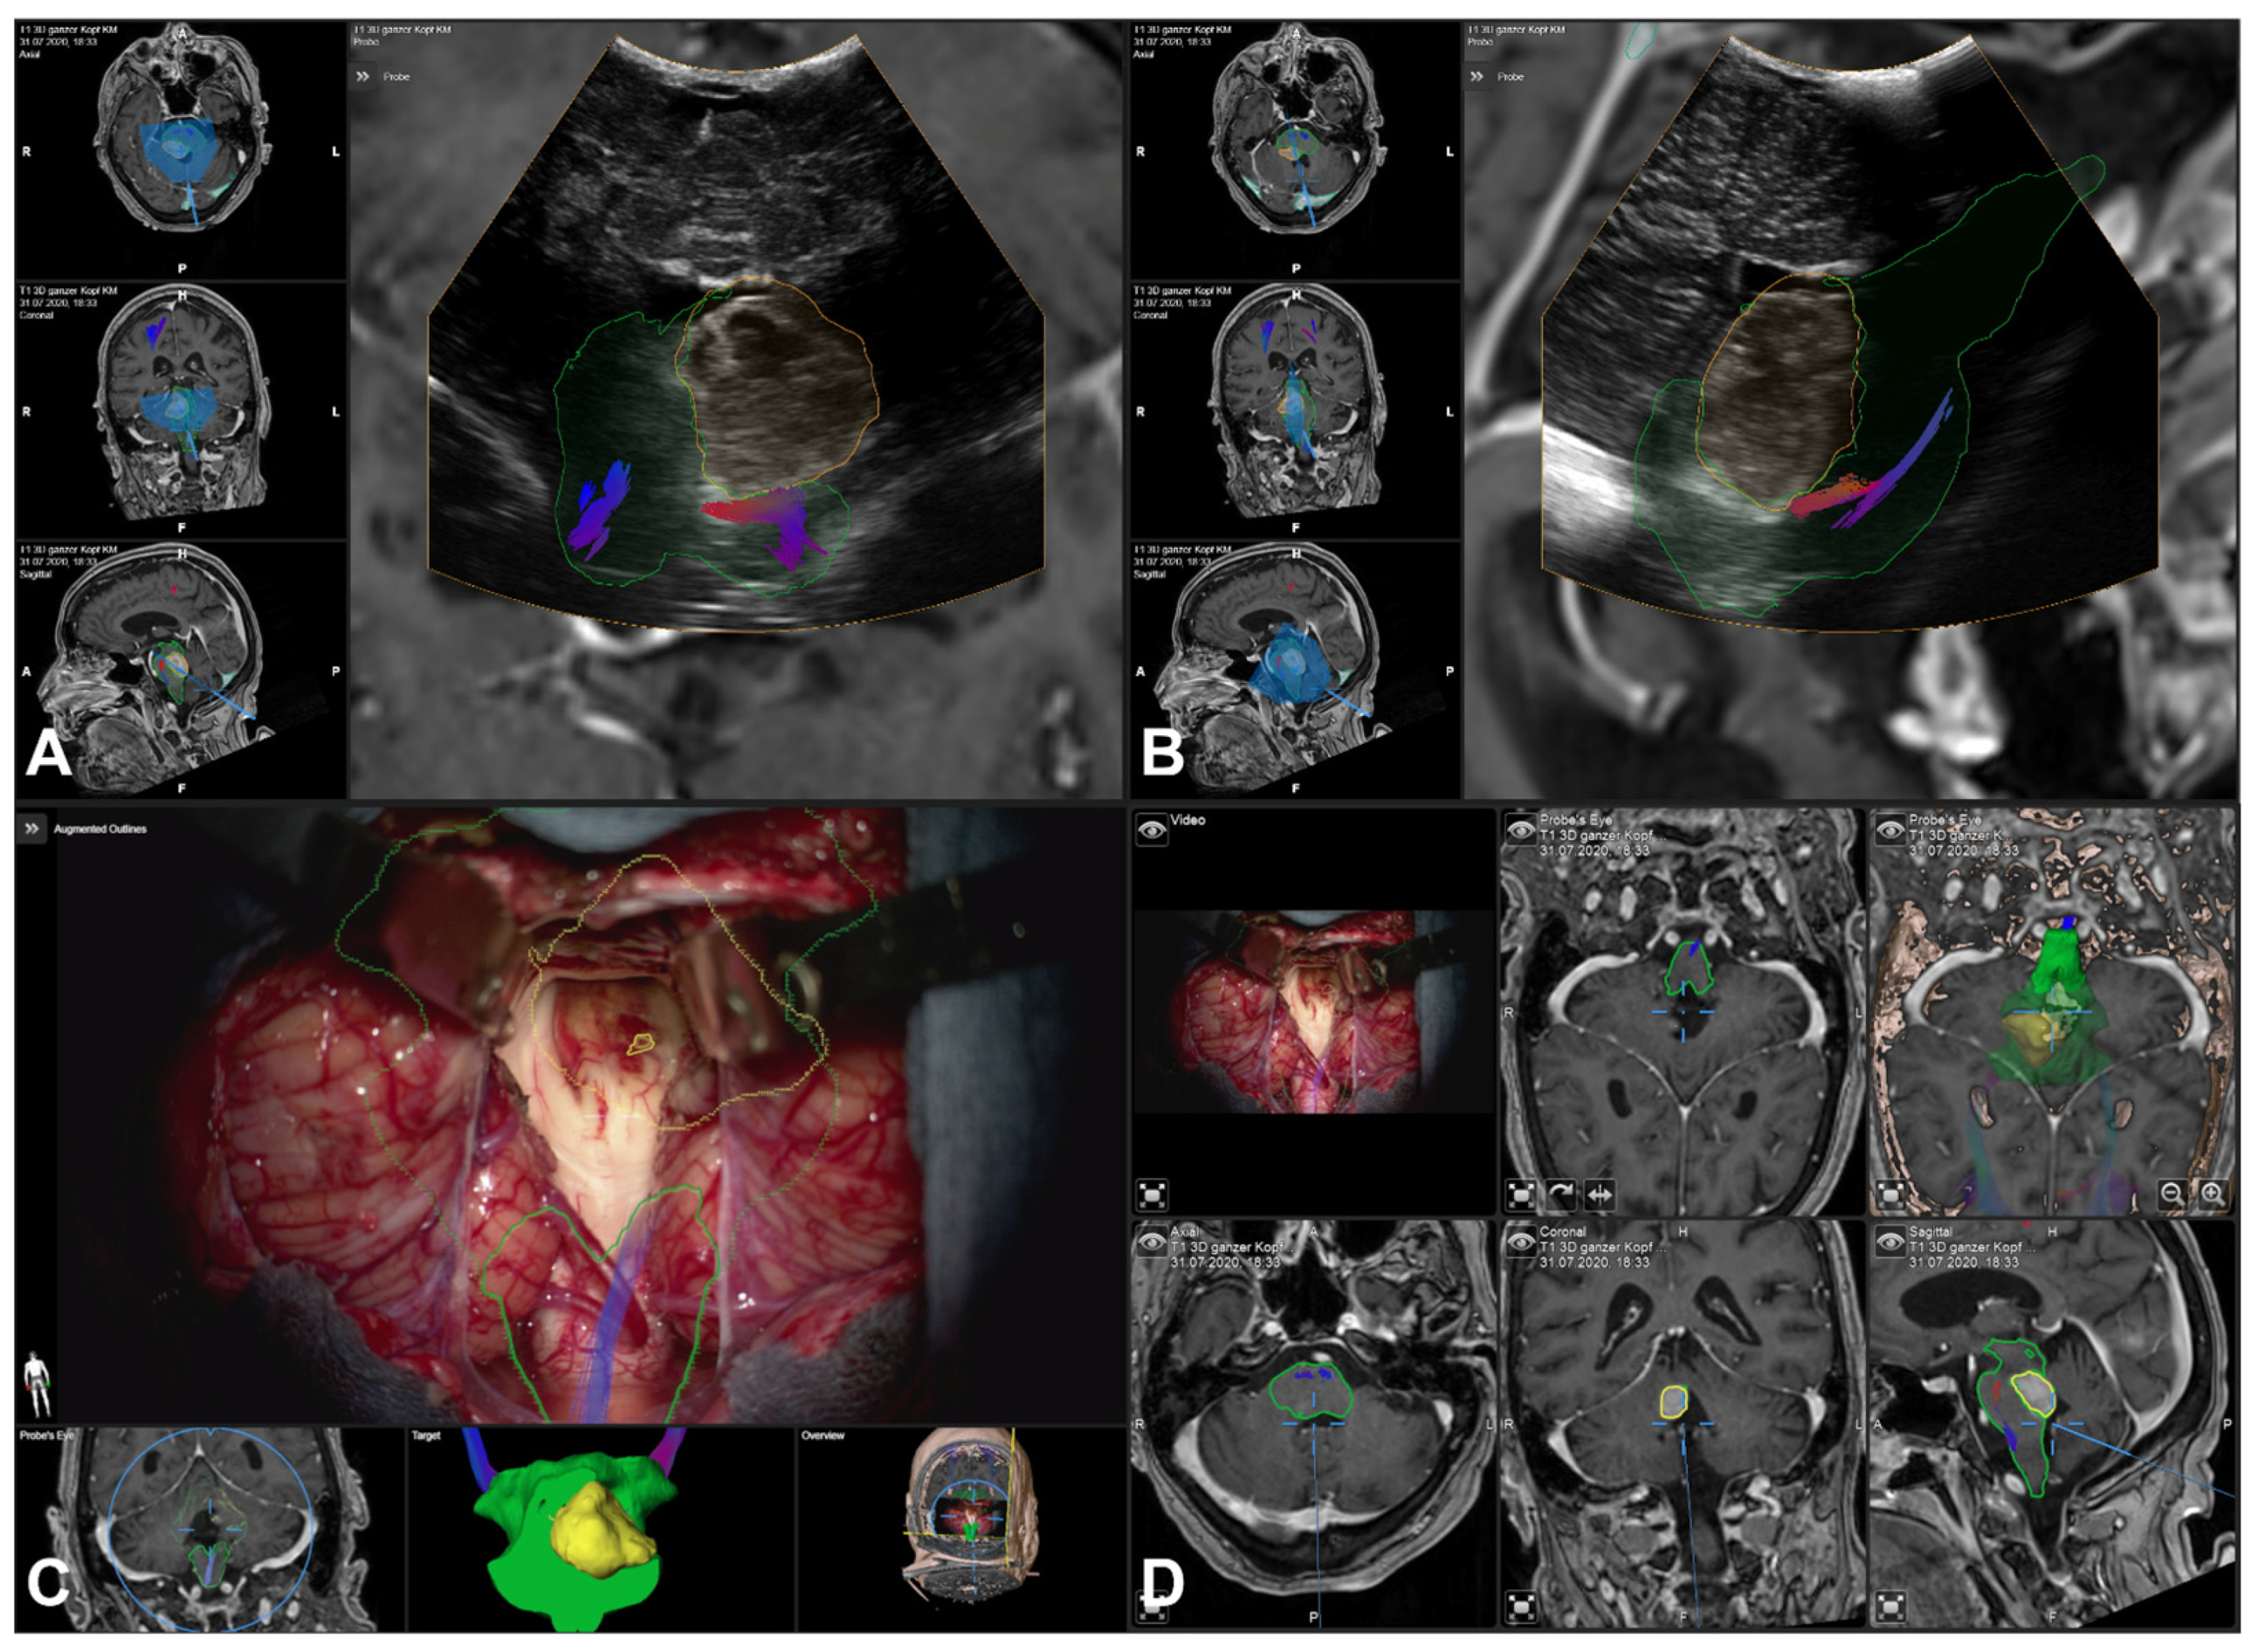

3.5. Illustrative Cases